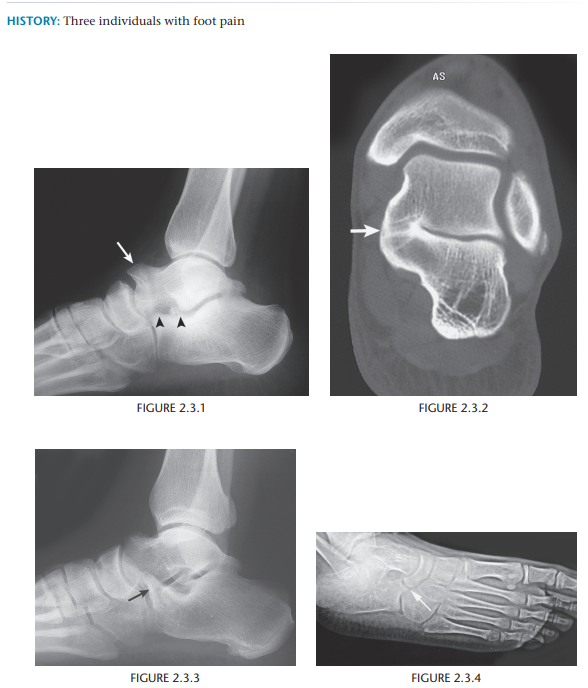

Tarsal Coalition